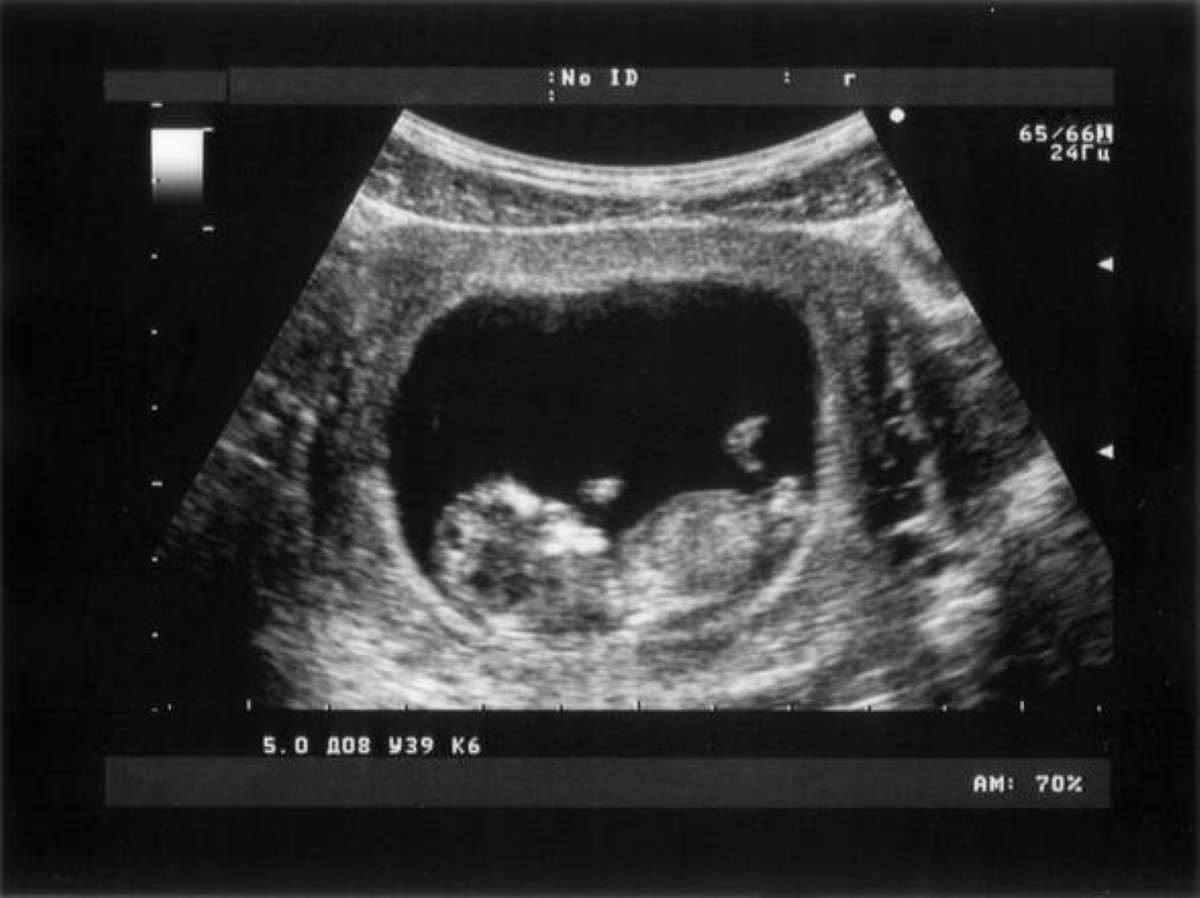

Ecografia senza contatto: la nuova tecnica utile per neonati e ustionati Salute Ecografia senza contatto: la nuova tecnica utile per neonati e ustionati admin Dicembre 24, 2019 ROMA – Arriva l’ecografia di ultima generazione, quella che non richiede il contatto con il corpo. Una...Read More